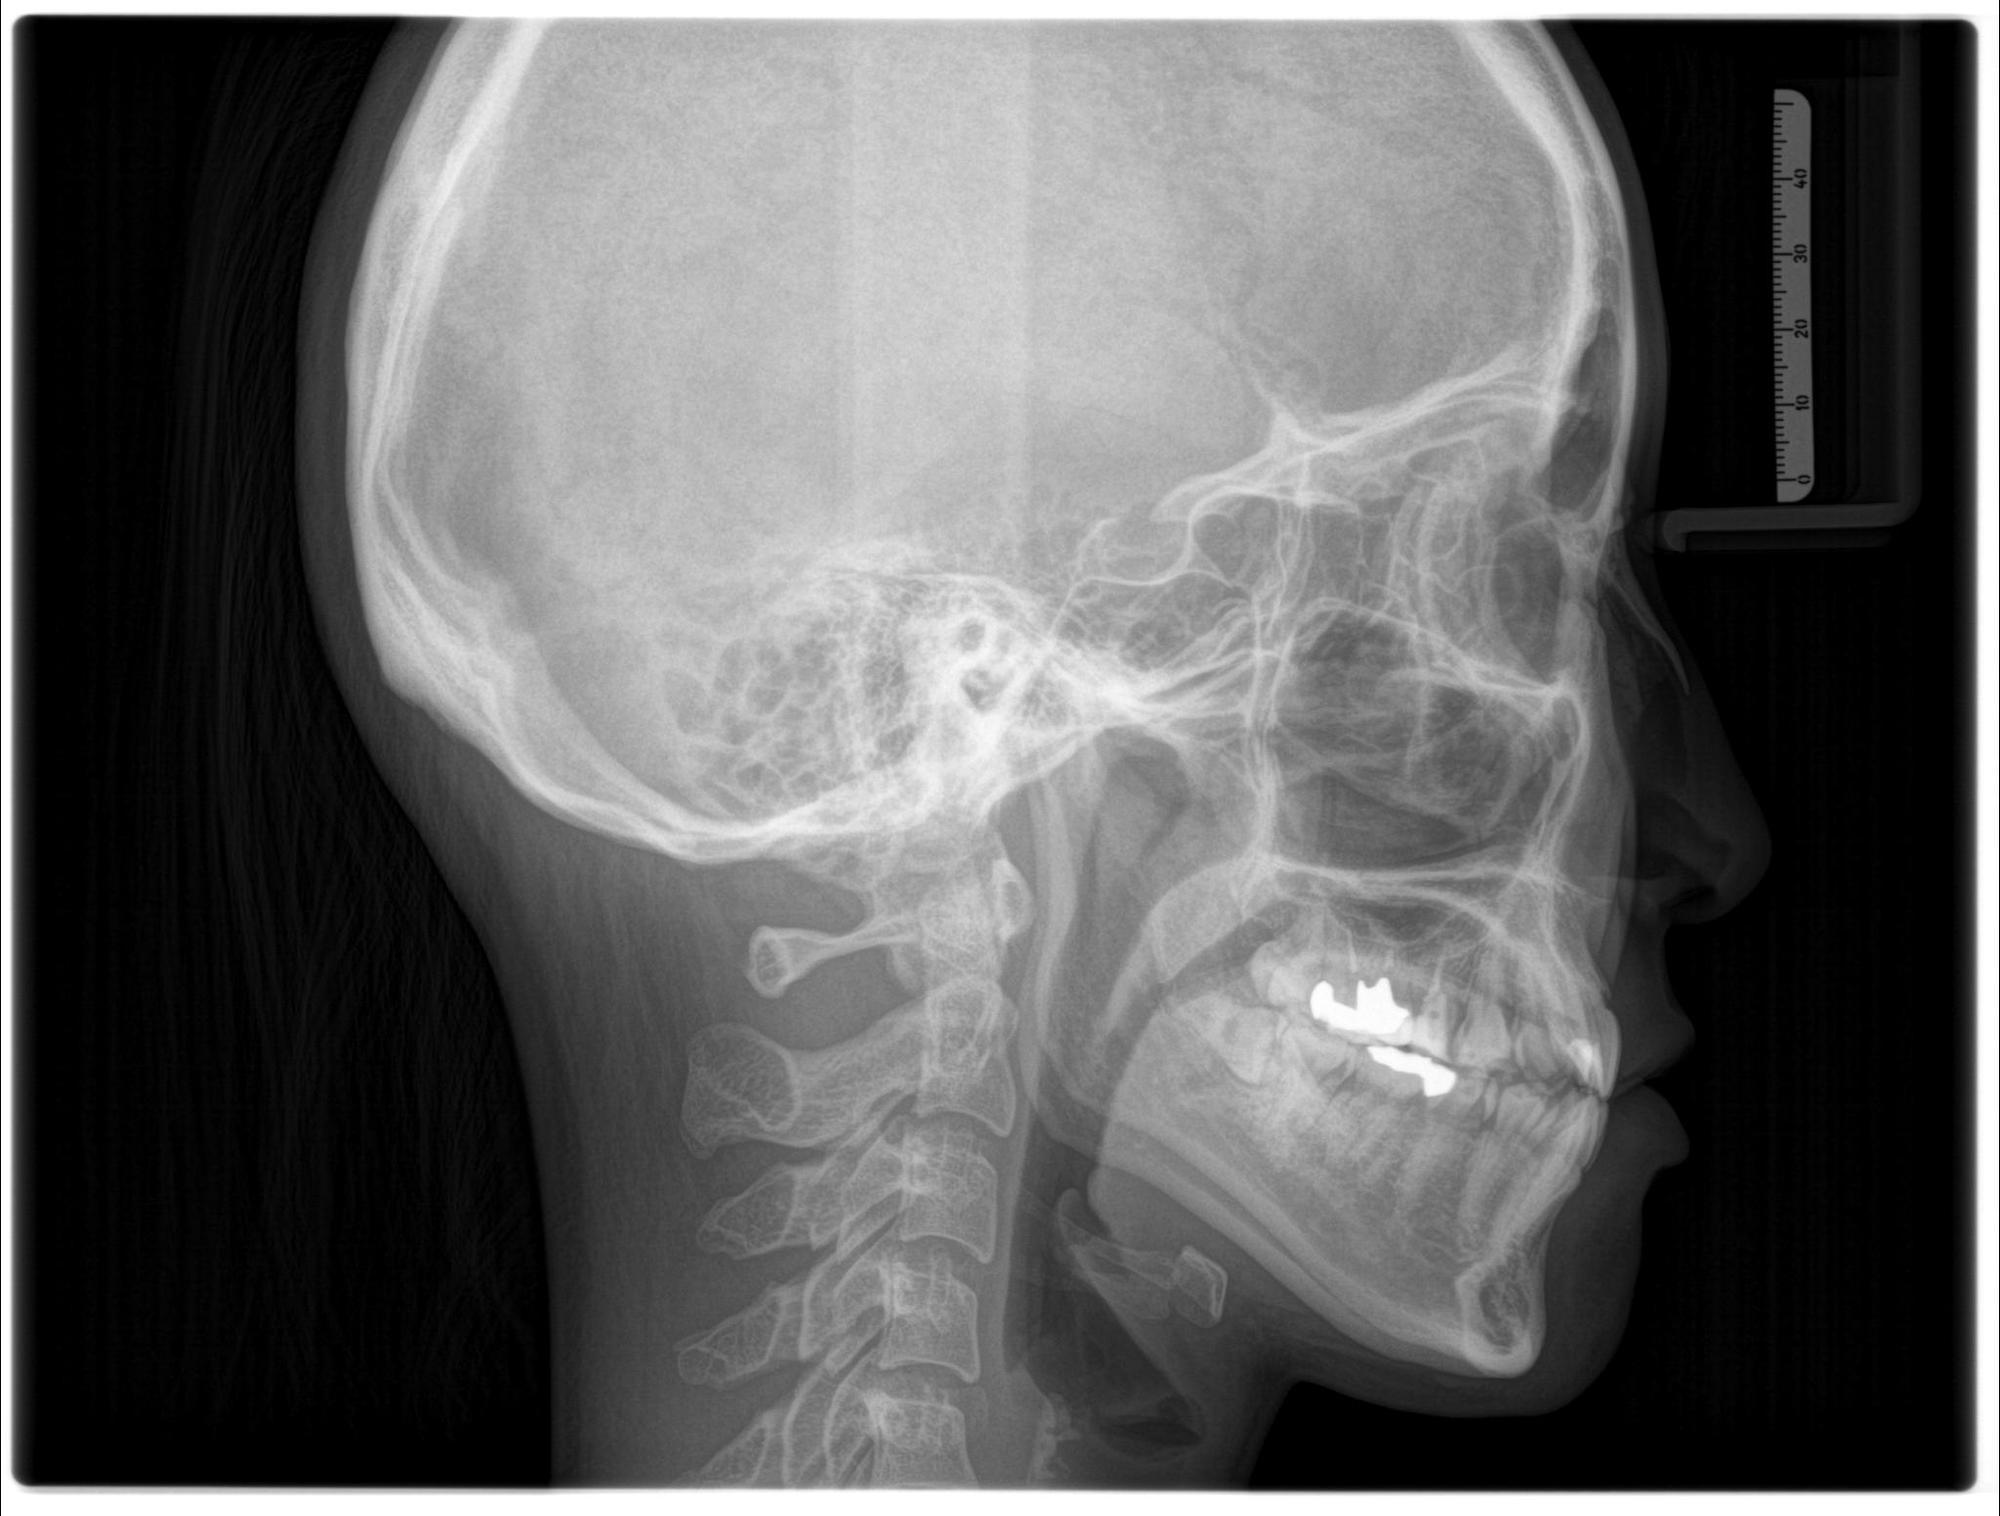

新しく『セファロ』とよばれる

矯正専用レントゲン機器を

導入いたしました。

正式には「頭部X線規格写真」といいます。

矯正治療を行う際に

頭を基準として歯の傾き

顎骨・歯列の位置などを

確認することができます。